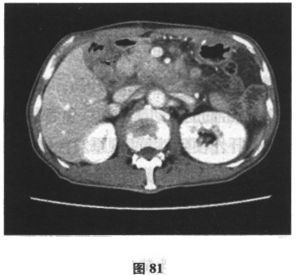

患者男,71岁,因“反复腹胀、纳差6个月,加重伴尿色加重1周余”入院。患者6月前开始肝中上腹胀,进食后加重伴纳差,就诊后予保护胃黏膜治疗症状无缓解。近一月来患者腹胀、纳差较前加重,门诊行胃镜及活检检查示慢性中度萎缩性胃炎伴肠化生,呼气试验示Hp(+),予三联方案(兰索拉唑、左氧氟沙星、克拉霉素)进行Hp根除治疗(该患者青霉素皮试+),停药4周后复查呼气试验示仍(+),调整抗生素后予四联疗法(奥美拉唑、左氧氟沙星、果胶铋、克拉霉素)继续根除治疗,但服药疗程未结束时患者腹胀、纳差加重,伴恶心、呕吐,尿色如浓茶样,伴皮肤黄染,于门诊查肝功能示总胆红素113.7μmol/L,结合胆红素64.5μmol/L,ALT110U/L,AST72U/L,尿常规:胆红素(++)。近2个月体重减轻7.5kg。患者既往于2年前有“肺大疱手术”史,有高血压史6月余,血压最高150/90mmHg,未规律服药。查体:神清,精神尚可,体型消瘦,皮肤巩膜明显黄染,未见肝掌、蜘蛛痣,腹软,无压痛,未及包块,双下肢无水肿。腹部B超未见异常。提示患者进一步检查示肝炎病毒指标、自身抗体均阴性。上腹部增强CT示:胆囊炎,肝内胆管稍扩张(图80),胰腺饱满(图81、图82),肠系膜、后腹膜淋巴结肿大(图83)。胸片显示患者肺部有术后金属物质。根据下面的检查提示,患者可能的诊断是什么?应进一步行何种检查()